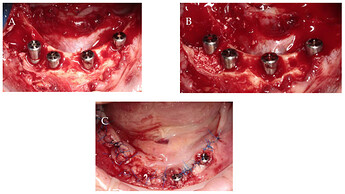

Surgical procedure: (A) implant insertion; (B) bone augmentation; (C) flap repositioning and suturing.